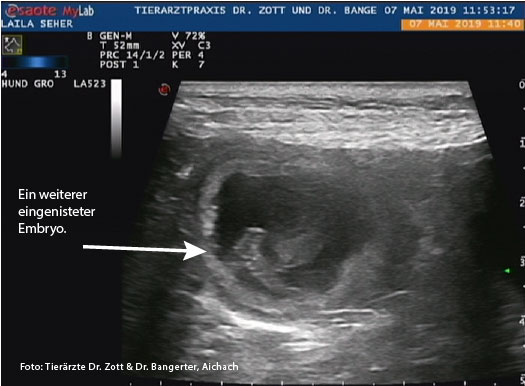

07. Mai 2019

Ultraschall beim Tierarzt.

Ein Herz! Man sieht ein kleines Herz schlagen!!!

JUHU! Wir sind schwanger!

Die Gesamtzahl der Welpen ist derzeit noch nicht feststellbar.